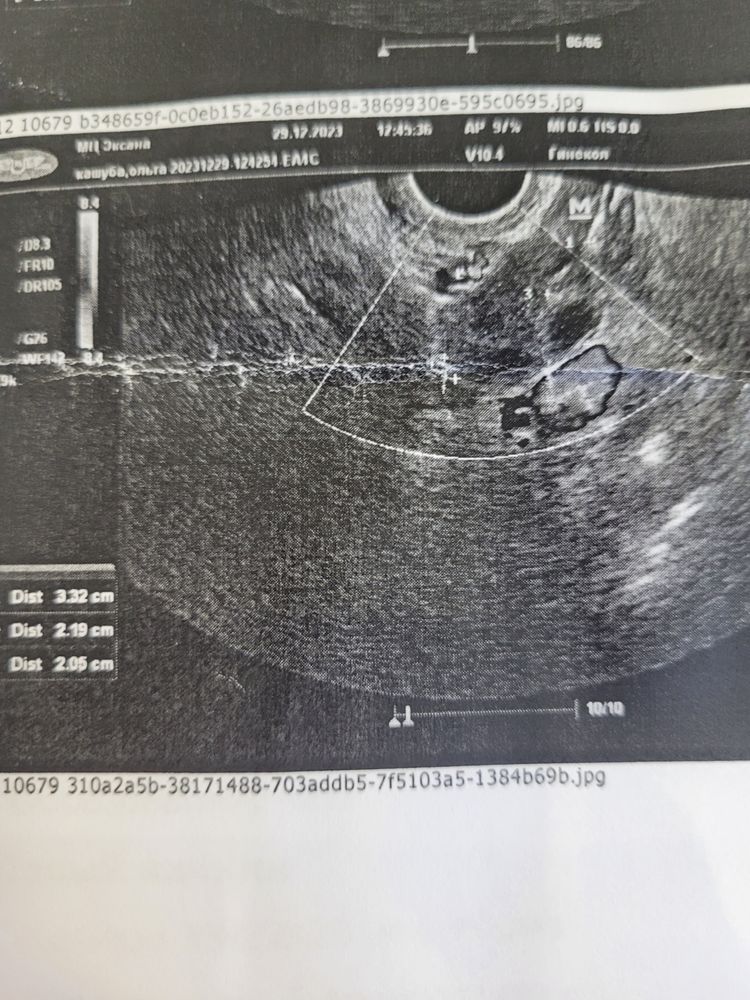

Olgita Kashuba в Хочу малыша 2 года Что такое жёлтое тело? Кто разбирается в узи. Это жёлтое тело? Посмотрите еще 20 записей на эту тему Отменить Ответить Нина У ЖТ рваные нечёткие края, часто неправильной формы. 29.12.2023 Ответить Olgita Kashuba Нина, бывают разные жёлтые тела. У меня обычно тоже звёздочка. Вот закралось подозрение поэтому. 29.12.2023 Ответить Olgita Kashuba 29.12.2023 Ответить Валерия Александрова а фото где 29.12.2023 Ответить Olgita Kashuba Валерия Александрова, забыла прекрепить. Вот. 29.12.2023 Ответить Орви 10 недель Спасибо, дедушка мороз 🥰 Чаты Беременных Выберите чат: Январята-2026 Февралята-2026 Мартята-2026 Апрелята-2026 Майчата-2026 Июнята-2026 Июлята-2026 Августята-2026